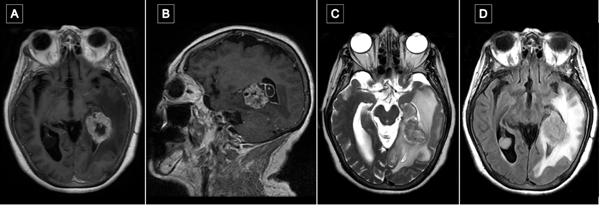

Transcurrido un mes de la cirugía, se realizó resonancia magnética de encéfalo con gadolinio en la que se observó en la región temporomesial izquierda un área de señal líquida con signos de gliosis periférica y sutiles restos de hemosiderina, sin evidencia de lesión tumoral residual. Persistía el edema vasogénico con efecto de masa sobre el sistema ventricular ipsilateral (Figura 6).

Figura 6. Comparación de resonancias magnéticas pre y postquirúrgicas. A y B) RM prequirúrgica de encéfalo, cortes axial y sagital, respectivamente, en secuencia T1 contrastada, se evidencia lesión expansiva con realce heterogéneo localizada en topografía temporomesial izquierda. C y D) RM de encéfalo con gadolinio realizada aproximadamente un mes luego de la intervención quirúrgica. Cortes axial y sagital, respectivamente, en secuencia T1 contrastada en la que se evidencia en región temporomesial izquierda un área de señal líquida con signos de gliosis periférica, sin evidencia de lesión tumoral residual.

Los cortes histológicos mostraron una proliferación neoplásica metastásica constituida por un adenocarcinoma bien diferenciado, con células de núcleo vesiculoso y amplio citoplasma eosinofílico, con tendencia a la formación de luces glandulares. Se observaron también extensas áreas de necrosis. Se realizó inmunomarcación para CK, GATA3, CDX2 y TTF1; se evidenció el siguiente patrón de marcación tumoral: CK +++, GATA3 (-), CDX2 (-) y TTF1 (-). Los hallazgos histopatológicos fueron compatibles con metástasis de adenocarcinoma bien diferenciado. Con estos resultados, se indicaron estudios complementarios en búsqueda de lesión primaria. Como hallazgo positivo de una videoendoscopia digestiva alta, se detectaron células atípicas en cardias, sugestivas de cáncer neuroendocrino.